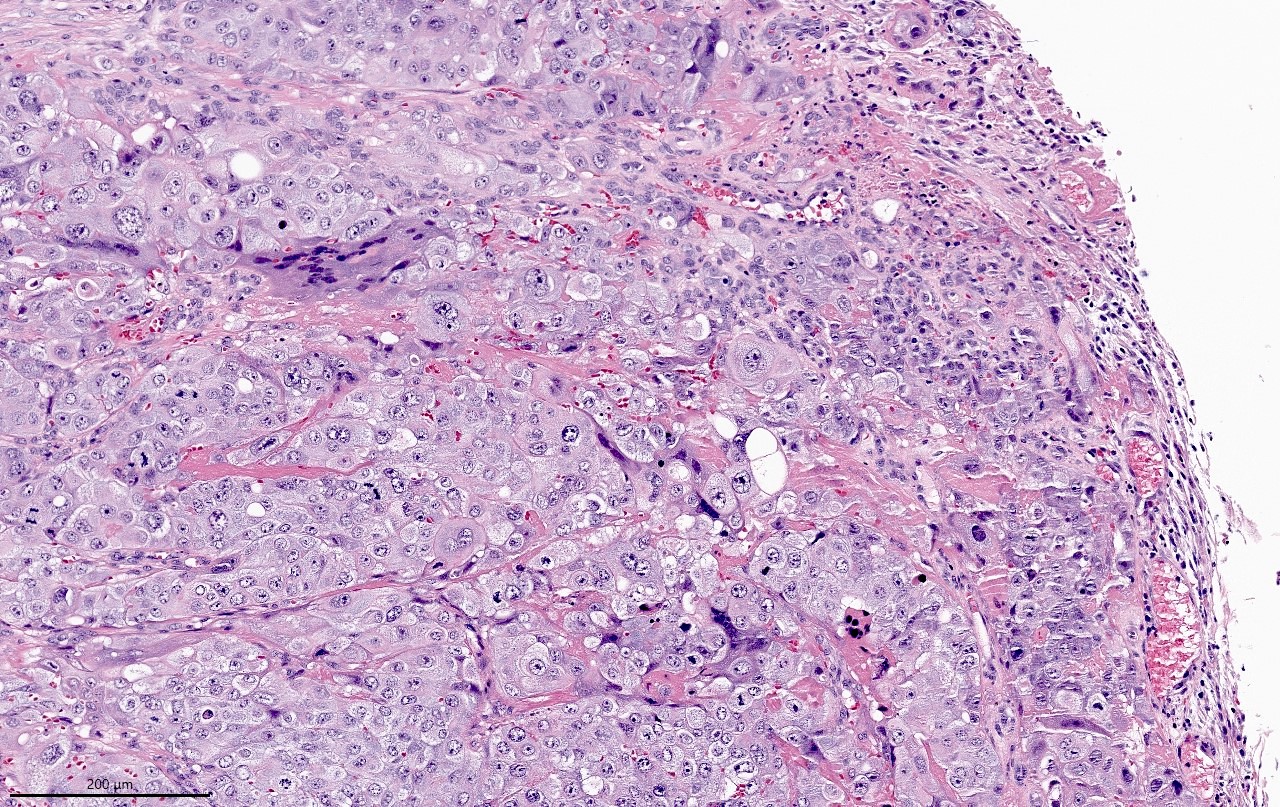

- Wide spectrum of trophoblastic differentiation, ranging from scattered isolated cells with trophoblastic differentiation to pure choriocarcinoma

- Often admixed with conventional urothelial carcinoma or other variants / subtypes

- When present as scattered isolated cells, they can be in the form of cytotrophoblasts (usually indistinguishable from high grade urothelial carcinoma or syncytiotrophoblast (recognizable by their multinucleated giant cells)

- Resembles choriocarcinoma in other organs

Microscopic (histologic) images